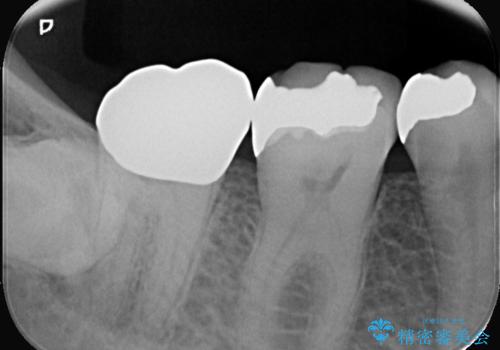

- 以前治療した右下7番(奥歯)のインレー(詰め物)が欠けてしまったことを主訴にご来院されました。診査の結果、残っている歯質が少なく、通常の詰め物では再び歯が割れてしまう破折リスクが高いと診断しました。このリスクを回避し、強い咬合力に耐えられるよう、歯全体を覆うクラウン(被せ物)による修復を提案。素材には、強度と適合性に優れたPGA(白金加金)クラウンを選択し、長期的に安定した奥歯の機能回復を目指しました。

治療ではまず、欠けた部分を修復し、歯全体を均一に形成しました。その後、PGA(白金加金)クラウンを作製・装着しました。

強度: 非常に高い強度を持つため、奥歯の強い咬合力にも耐え、歯の破折を効果的に防ぎます。

適合性: 歯への適合性が非常に高く、精密に隙間なく装着できるため、被せ物の下からの二次的な虫歯のリスクを最小限に抑えられます。

この治療により、欠けてしまった歯の構造的な弱点が解消され、患者様は硬いものでもしっかりと噛める、安心で機能的な奥歯を取り戻すことができました。